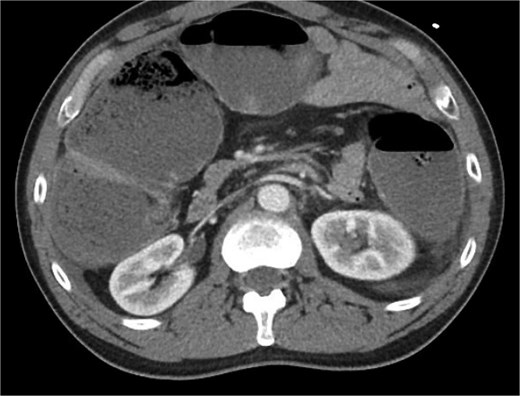

The patient was a 49-year-old male with a past medical history of anxiety and constipation who originally presented to the emergency department complaining of 1 day of worsening generalized abdominal pain, obstipation, nausea, and chills. Of note, he had undergone a colonoscopy 3 months prior to presentation, where two benign polyps were removed. There were no signs of inflammatory bowel disease. Upon examination, he was noted to be tachycardic to 130, with a blood pressure of 90/70 after 2 L of intravenous fluid resuscitation. His abdomen was distended and diffusely tender with peritoneal signs. Laboratory analysis showed a white blood cell count of 26 000, creatinine of 1.8, and a lactic acid of 7.9. A CT of the abdomen/pelvis revealed a cecum of 12 cm filled with liquid stool, but no pneumoperitoneum, pneumatosis, or colonic wall thickening. Figures 1 and 2 demonstrate the axial and coronal images of the dilated colon, respectively.

Coronal imaging demonstrating significant colonic dilation up to 11.9 cm in the cecum.